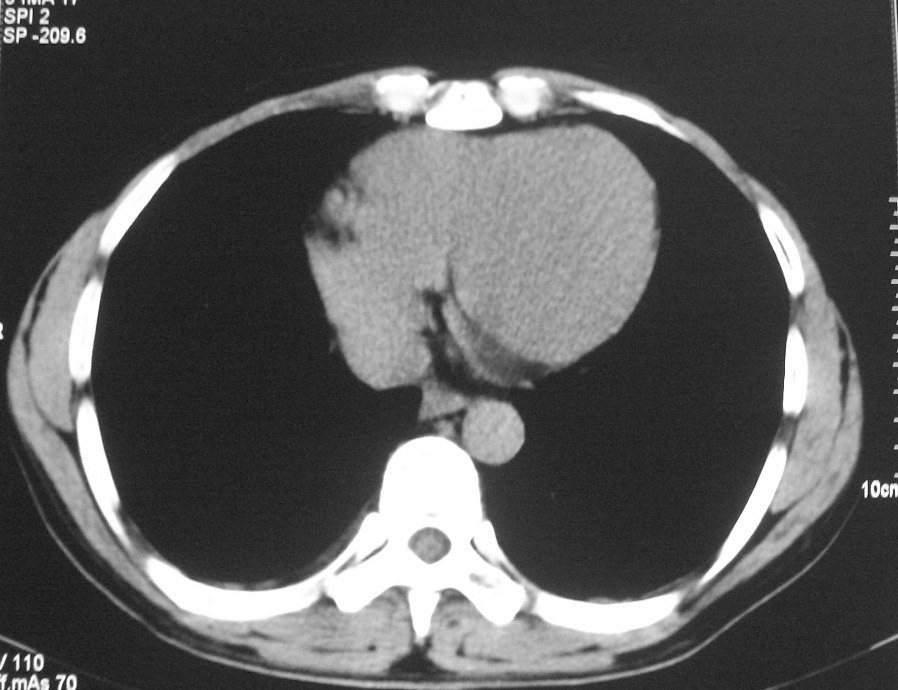

标题: CT5485:[原创]肺部占位请讨论

右上肺ca并肺不张,纵隔淋巴结转移

右肺上叶中央型肺癌并上叶肺不张、纵隔淋巴结肿大

右上叶支气管后壁明显增厚,支持右肺上叶中央型肺癌伴右上叶肺不张、纵隔淋巴结肿大。

考虑右上肺癌并肺不张,纵隔淋巴结转移

右上叶支气管后壁明显增厚,支持右肺上叶中央型肺癌伴右上叶肺不张、纵隔淋巴结肿大。建议支气管镜检查。

右上肺中央性肺癌伴右侧胸腔少量积液!右上肺胸膜下还有一小病灶,不完全排除结核,但个人支持恶性肿瘤!建议早穿刺活检。

右上叶支气管开口变窄,纵隔见肿大的淋巴结。支持右上叶中心型肺癌并右上叶不张纵隔淋巴结肿大。

右肺上叶中央型肺癌并上叶肺不张、纵隔淋巴结肿大.右侧少量胸腔积液。

右上肺中心型肺癌并肺不张,纵膈淋巴结肿大。右侧少量胸腔积液。

右肺上叶支气管后壁增厚,呈鼠尾状狭窄,纵隔内未见明显增大的淋巴结影,考虑为中央型肺癌伴右上肺不张